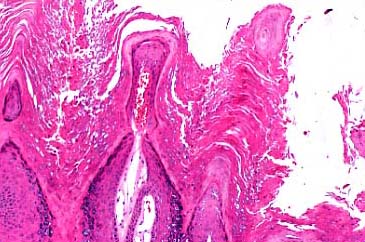

Verruca vulgaris = الثؤلول الشائع